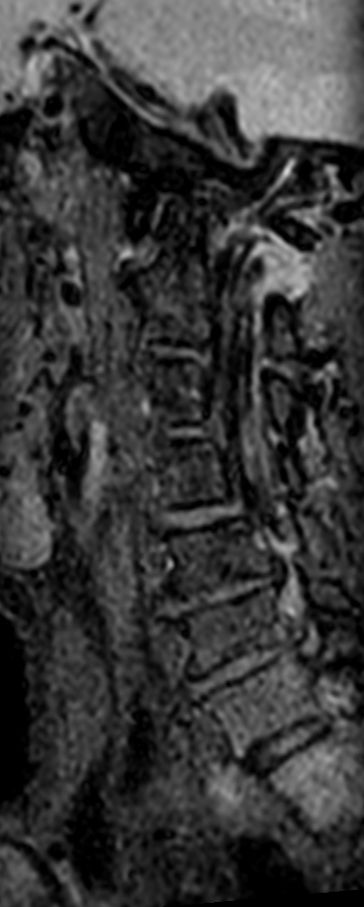

Neck stenosis

Patient with a neck stenosis. Compressed SENSE is used to shorten the total exam time.

3D T2w TSE Black Blood - Compressed SENSE